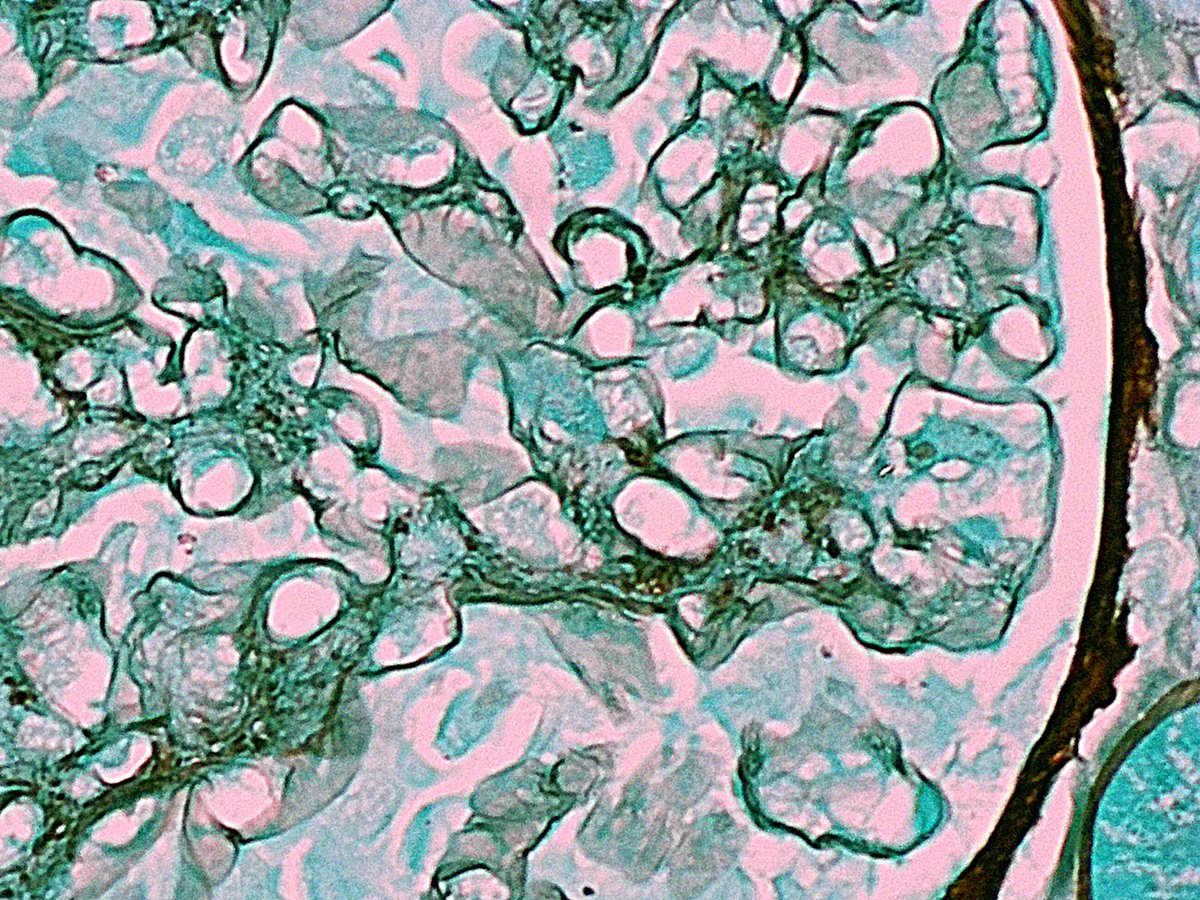

Mujer 👩 47 años Con App: Fibromialgia ????? Debuta con HTA hace 2 meses Proteinuria 24h : 2083.0 mg Ana: positivo Resto inmunológico : negativo Biopsia Renal :

8

9

52

Vamos a hacer una Biopsia ! Y de repente ! Que es esooooooooo?